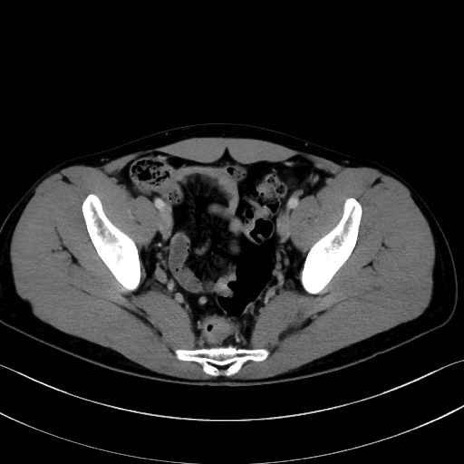

内閉鎖筋(obturator internus) のCT画像の解剖

内閉鎖筋 (Obturator internus)